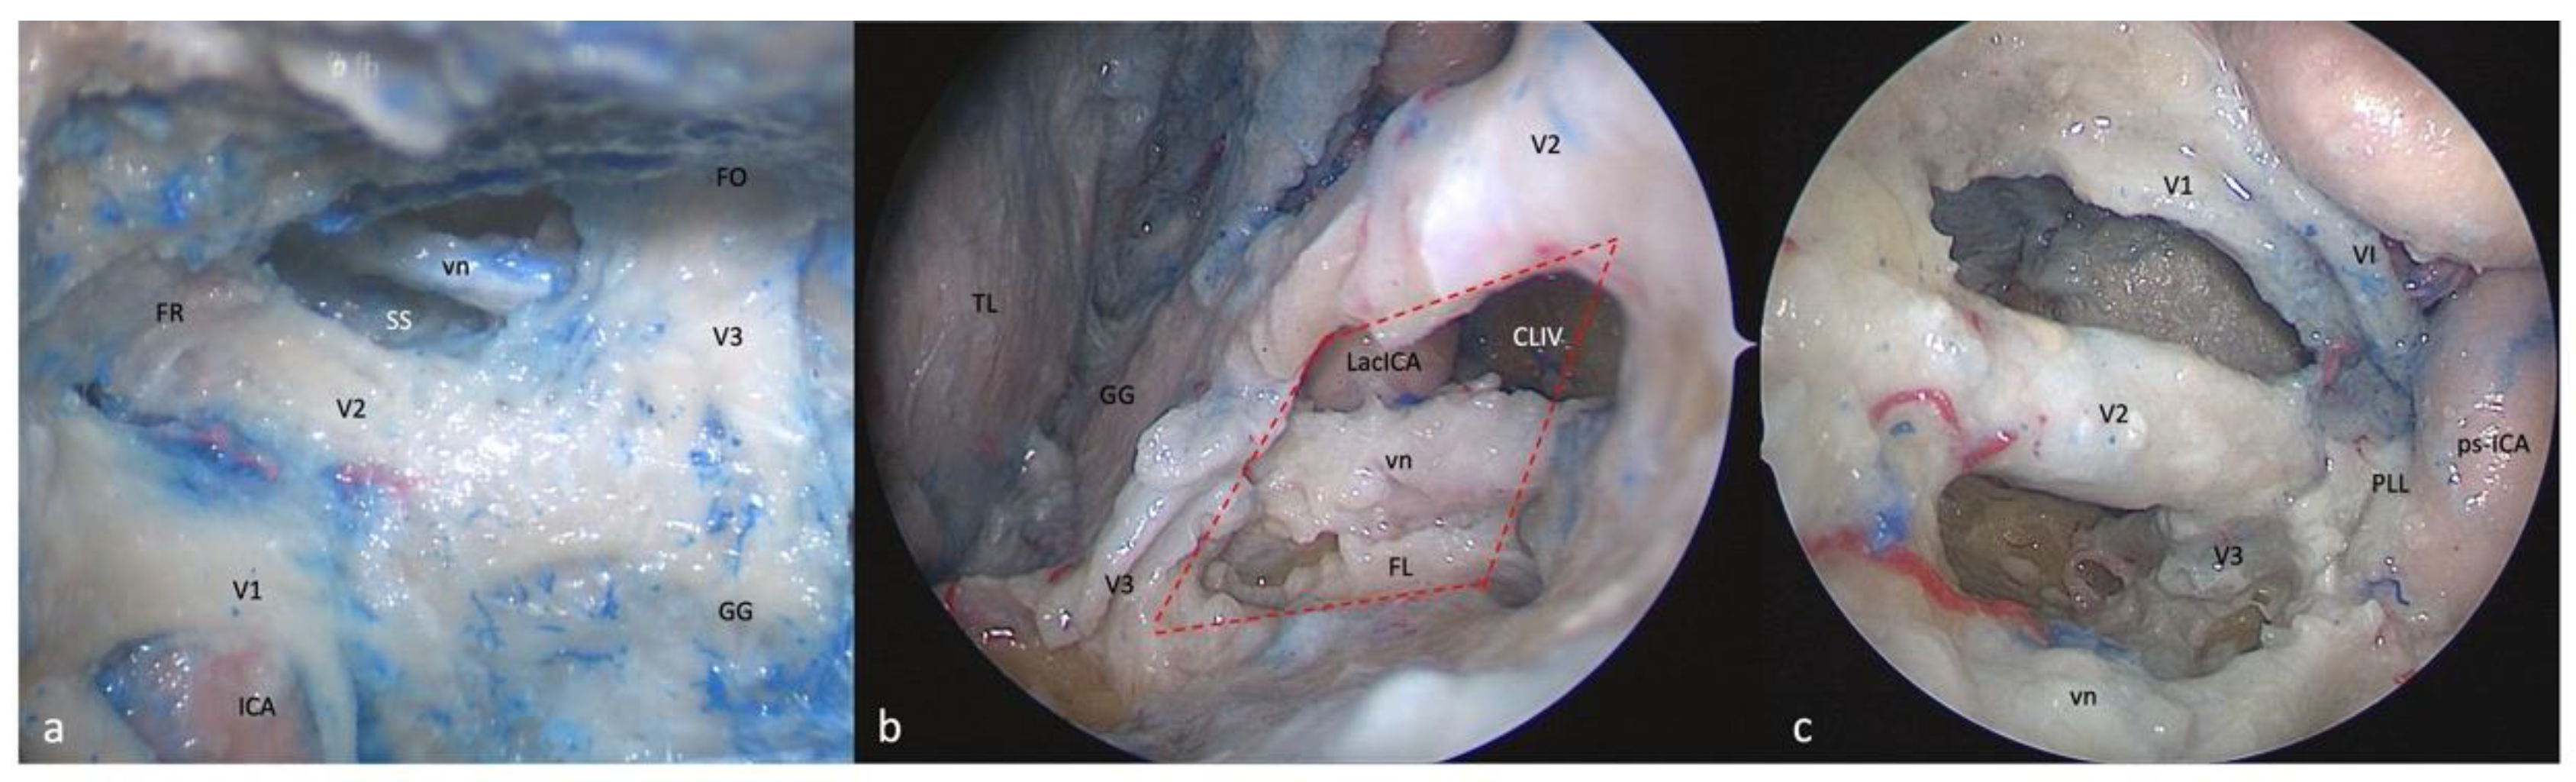

3.5. Anteromedial Triangle (Mullan’s Triangle)

3.5.1. FTOZ Perspective

3.5.2. SETOA Perspective

3.5.3. EEEA Perspective

3.6. Anterolateral Triangle

3.6.1. FTOZ Perspective

3.6.2. SETOA Perspective

- (a)

- A wider superior window (“supravidian”) that discloses two corridors in relationship to the lacerum segments of the ICA: a “medial supravidian corridor” leading to the lower clivus, and a “lateral supravidian corridor” leading, after gentle lateralization of the Gasserian ganglion, to the medial aspect of the Meckel’s cave and the terminal portion of the horizontal petrous ICA (pICA).

- (b)

- A narrow inferior window (“infravidian”) that includes the inferior portion of the foramen lacerum distally, and the sphenoid sinus proximally.

3.6.3. EEEA Perspective